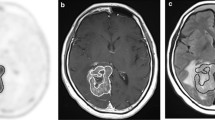

Magnetic resonance imaging

MR images after contrast enhancement were used to evaluate BBB breakdown in the tumor and to identify exact lesion location. T1-weighted MR images with 0.1 mmol/kg gadolinium diethylenetriaminepentaacetic acid (Gd-DTPA) were obtained using a 1.5-T whole-body MR imaging unit (Signa Advantage, GE Medical Systems, Milwaukee, WI, USA, or VISART, Toshiba, Tokyo, Japan). The degree of Gd enhancement in the tumor on T1-weighted MR images was evaluated visually by comparing the intensity of lesion enhancement with that of the normal choroid plexus [19]. Gd enhancement in tumors was graded as score 0 (none), score 1 (less than that of choroid plexus), score 2 (equal to choroid plexus), and score 3 (more than choroid plexus).

[18F]-FLT and BBB permeability

A previous study showed that the major portion of [18F]-FLT uptake is similar to the low levels observed in unenhanced lesions on MR imaging and demonstrates inside the volume of increased permeability defined by MR imaging T1-weighted Gd enhancement [26]. In this study, gliomas with no MR imaging T1-weighted Gd enhancement had low accumulation on [18F]-FLT PET images compared with those with enhancement, and there was a good correlation between [18F]-FLT PET images (SUVmax, T/N ratio) and Gd-enhanced MR imaging. In general, Gd contrast enhancement on T1-weighted MR images of brain lesions, such as tumor, necrotic tissue, and inflammation, is due to BBB disruption and increased blood vessel permeability [27]. It should be noted that there was some increase in T/N ratio for [18F]-FLT in tumors without Gd enhancement (Table 1), and this remains to be understood. [18F]-FLT can cross the BBB and plasma membranes; however, the mechanisms of transport and influx to tumor cells across the BBB in vivo have not been fully elucidated. To interpret [18F]-FLT PET images as a measure of cell proliferation, we need to understand the mechanisms that account for its transport, accumulation, and retention in tissues.